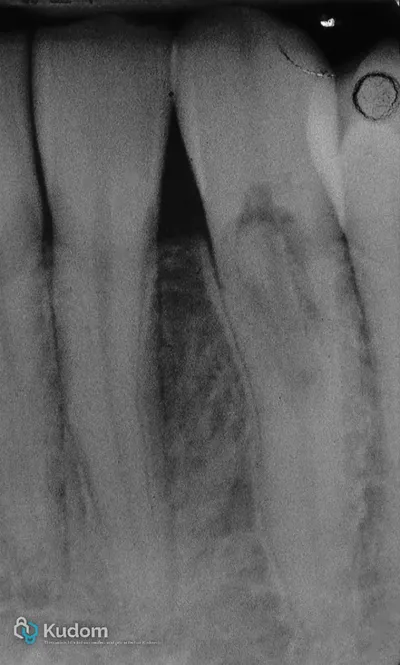

Gestione di riassorbimento esterno cervicale invasivo: iniziale trattamento ortogrado con riparazione interna in MTA. Dopo 15 anni, a causa di riattivazione, si esegue intervento chirurgico con isolamento a lembi aperti: rimozione del tessuto infiammatorio, riparazione del difetto con bioceramico putty, flow e composito. Dopo finishing e polishing, il lembo viene suturato.